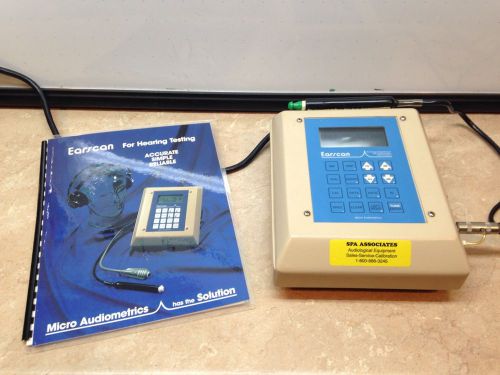

Earscan ES-T Tympanometer with Current Calibration Certificate